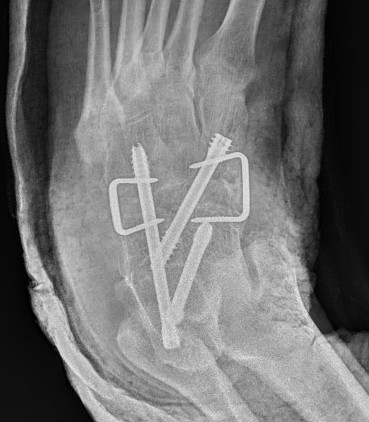

Open Middle Talocalcaneal bar resection +/- calcaneal lengthening osteotomy

Technique

Medial approach

- navicular tuberosity to medial border T Achilles

- 2cm superior to superior calcaneal tuberosity

- release flexor retinacular sheath

- elevate T Post and FDL tendon anteriorly

- neurovascular bundle and FHL retracted plantarward

- identify posterior facet

Resection

- can be difficult to identify normal identity

- protect subtalar joint

- remove more bone from talus than sustentaculum talus to preserve hindfoot stability

- insert fat graft / ITB allograft / half FHL

+/- calcaneal lenthening osteotomy

- use bone resected from coalition

- K wire to stabilize calcaneocuboid joint